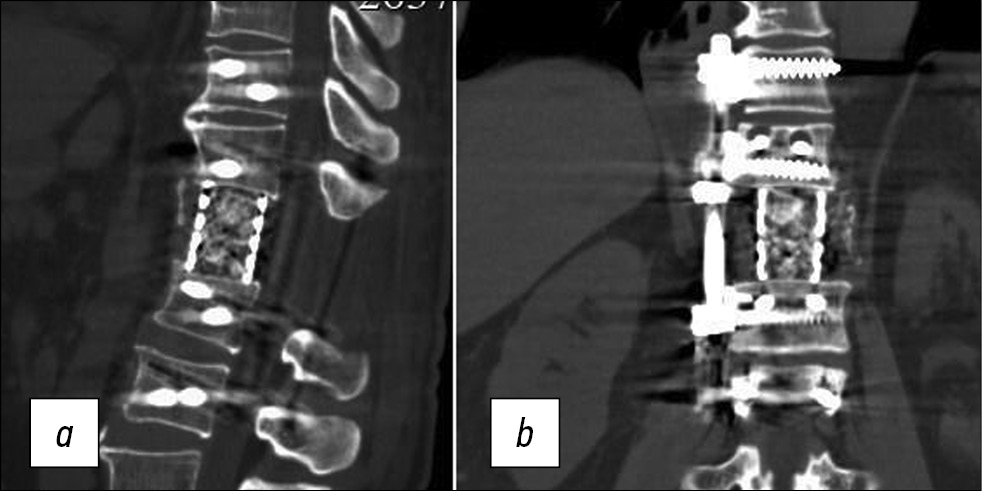

После операции отрицательной динамики в неврологическом статусе не выявлено. Плевральный дренаж удален на 4-е сутки. Со 2-х суток начата поэтапная активизация больного в вертикальном положении, а на 5-й день пациент уверенно ходил без дополнительной опоры. Контрольные рентгенография и КТ, выполненные на 10-е сутки, показали правильное расположение элементов металлоконструкции (рис. 3 и 4).

Рис. 3. Рентгенограммы позвоночника больного Е., 71 год, после операции, прямая (a) и боковая (b) проекции.

Рис. 4. Компьютерная томограмма позвоночника больного Е., 71 год, после операции, боковая (a) и прямая (b) проекции.